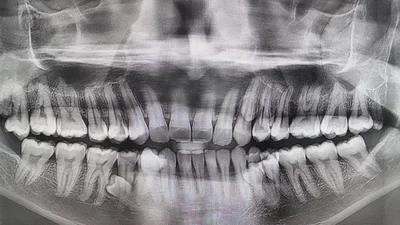

Чоловік має найбільшу кількість зубів у світі / Джерело: guinnessworldrecords

Чоловік із Малайзії здивував світ своєю незвичайною усмішкою – у його роті найбільша кількість зубів серед чоловіків у світі. Пратхаб Муніанді має 42 зуби, що на 10 більше, ніж у середньостатистичної людини, яка зазвичай має 32.

Його рекорд офіційно підтвердили у 2023 році після обстеження двома стоматологами. Цікаво, що лікарі також виявили ще два зуби, які поки не прорізалися. Пратхаб, який працює інженером у нафтово-газовій галузі, розповів, що вперше звернув увагу на незвичайну особливість у 2021 році під час сімейного чаювання. “Я сказав родині, що мені здається, ніби у мене ростуть зайві зуби. Ми разом їх порахували й виявили, що на той момент у мене було 38 зубів,” – пригадує він.